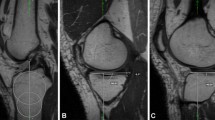

As compared to patients with no worsening of WORMS subscores over time (n = 5), patients with worsening of any WORMS subscore (n = 16) had more pathological patellar instability values (Figs. 2 and 3): Patients with worsening of WORMS subscores showed a lower trochlear depth (mean ± SEM; 4.4 ± 0.4 mm versus 6.2 ± 0.2 mm, P = 0.020), a lower medial-to-lateral trochlear facetal ratio (0.44 ± 0.13 versus 0.59 ± 0.10, P = 0.023), a higher TTTG distance (14.5 ± 0.8 mm versus 10.3 ± 2.3 mm, P = 0.040), and a higher postoperative lateral patellar tilt (13.9 ± 1.1° versus 5.7 ± 2.7°; P = 0.003). The difference for sulcus angle showed a statistical trend (147 ± 2° versus 138 ± 5°, P = 0.094). Significances persisted after adjustment for covariates. Patients with worsening of patellar cartilage lesions during follow-up presented a significantly lower trochlear depth (3.9 ± 0.8 mm versus 5.3 ± 0.3 mm, P = 0.046) and a larger sulcus angle (151 ± 5° versus 141 ± 2°, P = 0.039).

Comparison of the mean preoperative MR imaging-based patellar instability and trochlear dysplasia values between patients without progression of knee joint degeneration from baseline to follow-up (n = 5, depicted in green) and patients with progression of any WORMS subscore, indicating progression of knee joint degeneration from baseline to follow-up 2.3 years after MPFL reconstruction (n = 16, depicted in red). Average values, upper and lower boxes indicating the 2 and 3 quartile and upper and lower whisker indicating the range of the parameters. *P < 0.05